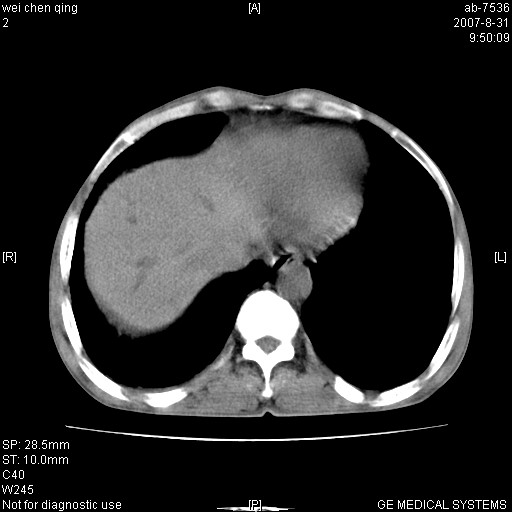

以下是引用zyyzzy在2007-8-31 14:34:00的发言:[br]该病人肝内胆管扩张,胆囊及胆总管未见明显扩张。在倒数第9层图像上可看到左右肝管结合部(肝总管)有软组织影,此处应薄层扫描。考虑肝总管占位(ca)、腹水。[br]